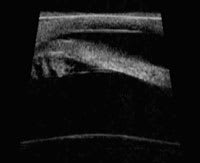

Model MHF: A high-frequency ultrasound of the anterior chamber angle and ciliary body. |

You can think of the portable ultrasonic device (Model MHF-1, Portable Ophthalmic Devices Inc.) as a portable version of the existing ultrasound biomicroscopy (UBM, Carl Zeiss Meditec) technology that uses a high-frequency transducer on the surface of the eye.

The Zeiss UBM and new version of the MHF-1 operate at 50MHz and can produce images with good resolution and a depth of penetration of the ocular tissue (4-5mm in depth). This is an advantage over the anterior segment OCT counterparts, which do not image as deeply.

This technology may improve imaging of conditions that occur behind the iris, such as tumors and the position of posterior chamber intraocular lenses, which may contribute to the pathogenesis of various forms of glaucoma. The Model MHF-1 portable ultrasonic device should receive approval from the FDA, for use in humans, in the near future.